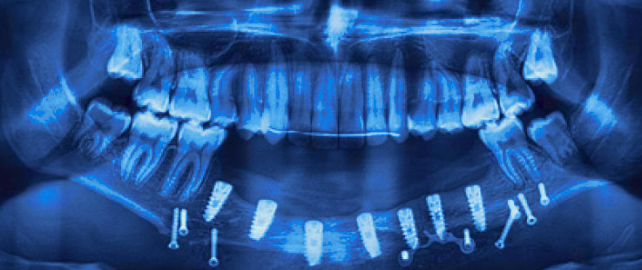

Персонифицированная реабилитация пациентов детского возраста с применением дентальных имплантатов